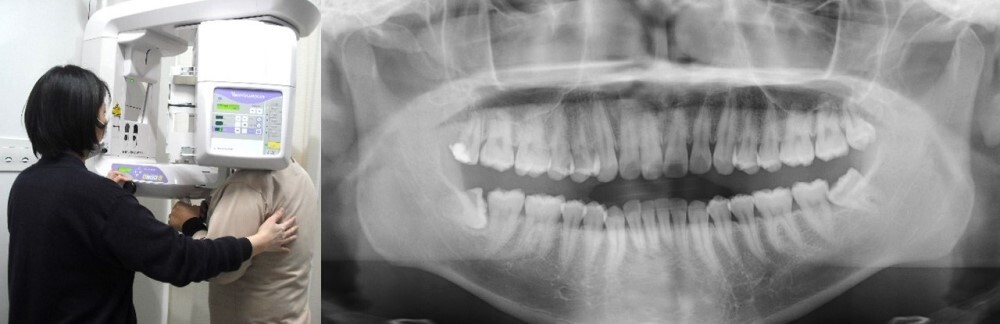

歯科パノラマ撮影検査

歯科パノラマ撮影検査は、歯や顎の骨の画像を撮影する検査です。装置が顔の周囲を回りながら撮影します。

写真:歯科パノラマ撮影